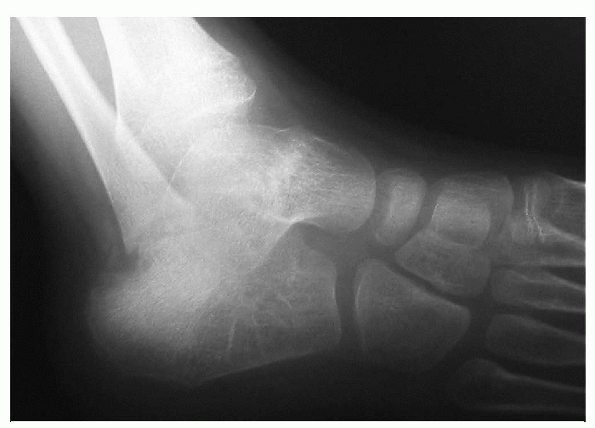

-

Partial or complete anterior displacement

of the radial head and subtle anterior bowing of the ulnar shaft on

lateral radiographs (ulna bow sign) are diagnostic. -

Other possible causes of anterior radial

head dislocations: cubitus varus after supracondylar fractures,

osteochondritis dissecans of the capitellum, and birth trauma. -

The mechanism of injury is the same as that for Monteggia injuries but without obvious ulna fracture.